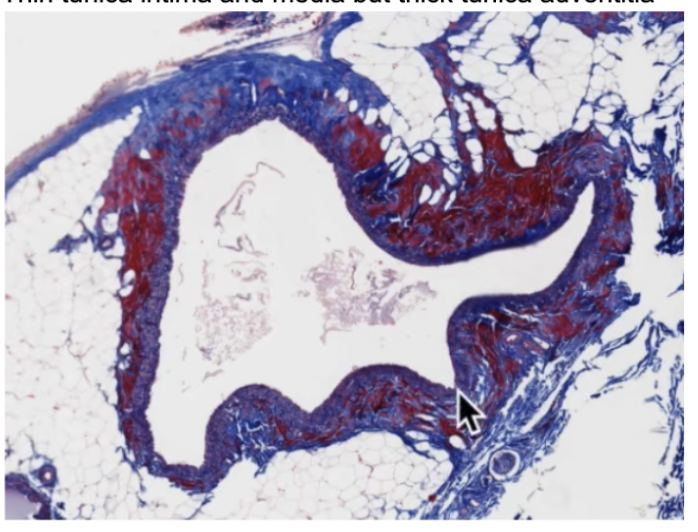

Medium veins

Thin tunica intima and media but thick tunica adventitia

medium vein with valve

Irregularly dispersed smooth muscle

No internal elastic lamellae

Valves are the extensions of tunica intima to break into small compartments for movement (skinny extensions in photo)